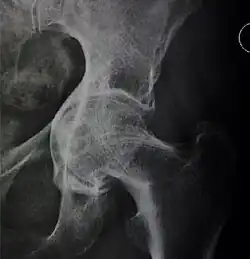

Measurements

- Fossa/ilioischial relationship: In normal conditions the floor of the acetabular fossa is lateral to the ilioischial line by 2 mm in men and 1 mm in women. When the acetabular floor overlaps or overpasses the ilioischial line, the diagnosis of coxa profunda can be made. Nevertheless, coxa profunda had been found in 76% of asymptomatic hips, mainly in women. Therefore, this as an isolate criterion is not enough to make the diagnosis of pincer-type impingement. A more severe condition is protrusio acetabuli, diagnosed when the femoral head overlaps or overpasses the ilioischial line.[3]